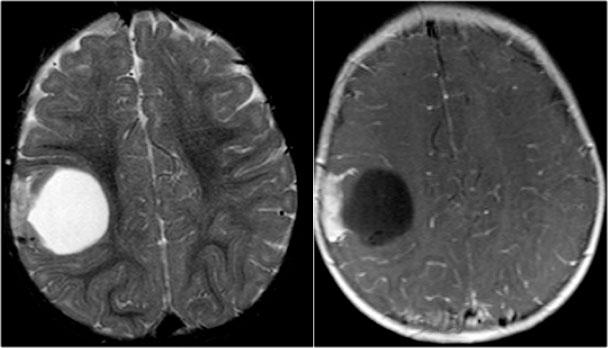

DNET

Dấu hiệu chính

- Hồi não phồng to

- Hình ảnh nang dạng bong bóng

- Có thể có hình nêm hướng về phía não thất

- Thường không hoặc chỉ ngấm thuốc rất ít

- Liên quan đến loạn sản vỏ não khu trú

DNET trong các trường hợp điển hình biểu hiện dưới dạng khối dạng bong bóng làm giãn rộng các hồi não bị tổn thương.

Hình ảnh nang dạng bong bóng được thể hiện bởi các cấu trúc nhỏ giống nang trong khối u, tăng tín hiệu rõ rệt trên chuỗi xung T2W.

DNET ở bé trai 11 tuổi biểu hiện với cơn động kinh cục bộ kháng trị.

Khối u cho thấy hình ảnh dạng bong bóng đặc trưng và có hình ảnh lõm xương sọ kín đáo.